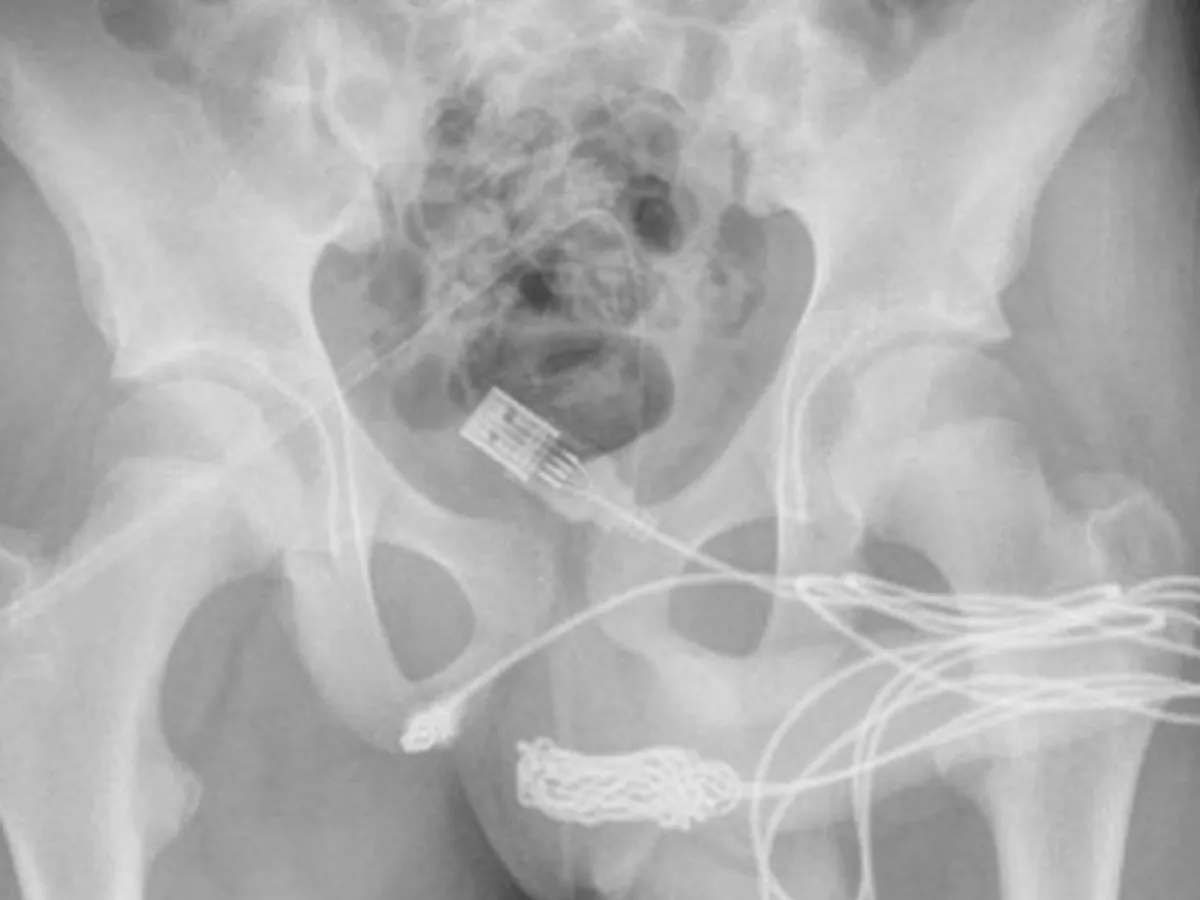

Medicii au scris: "S-a constatat că cele două porturi distale ale cablului USB ieșeau din meatul uretral extern, în timp ce partea din mijloc a cablului înnodat a rămas în interiorul uretrei.

"S-a făcut o incizie longitudinală peno-scrotală peste corpul străin palpabil și s-a efectuat o disecție atentă prin țesuturile mai profunde, despicând mușchiul bulbospongios.

"Ambele capete ale firului au fost scoase cu succes prin meatul uretral extern".

Medicii au folosit o tijă metalică pentru a scoate cablul, dar nodurile au dovedit că acest lucru este imposibil.

Într-un final, medicii au fost nevoiți să taie secțiunea dintre organele genitale și anus pentru a putea ajunge la cablu de dedesubt.